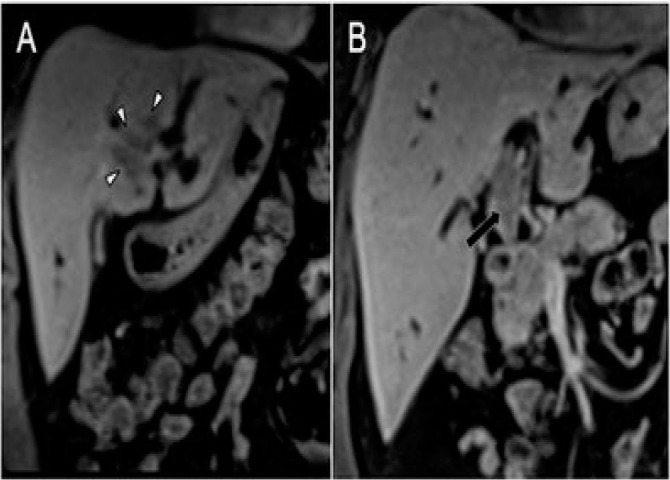

Abstract Image